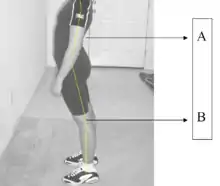

La lordosis patológica o hiperlordosis es un aumento de la curvatura de concavidad posterior o convexidad anterior. Es más frecuente en la región lumbar, en donde se define como una concavidad mayor a 60°, y se debe a múltiples causas congénitas, posturales, postquirúrgicas, traumáticas, neuromusculares, pélvicas entre otras. La columna vertebral se encorva hacia adelante, hace más prominente los glúteos y ocasiona dolor de espalda.[1]

Por extensión, esta deformación anómala suele acompañarse de una debilidad de la musculatura del tronco, en particular de la musculatura anterolateral del abdomen. Para compensar las alteraciones de la línea gravitacional normal, las mujeres experimentan una hiperlordosis pasajera durante la fase final del embarazo. Esta hiperlordosis puede ocasionar lumbago, pero la molestia desaparece de ordinario poco después del parto. La obesidad también es causa de lordosis y lumbalgia en ambos sexos, por el mayor peso del contenido abdominal, situado delante de la línea gravitatoria penil. El adelgazamiento corrige este problema.